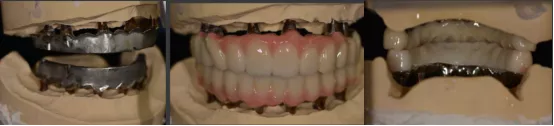

· 上下颌士卓曼360数字化导板 +预成临时修复体设计图。

· 士卓曼360导板包括:骨支持的基部导板 、牙支持的辅助导板 、就位于基部导板的种植导板 以及就位于基部导板的预成临时修复体组成。

· 最终修复体采用士卓曼原厂切削纯钛桥架+氧化锆整体桥。

· 临时修复体仓扫后回切设计纯钛桥架。

· 制作士卓曼原厂切削纯钛桥架+氧化锆整体桥+龈瓷。